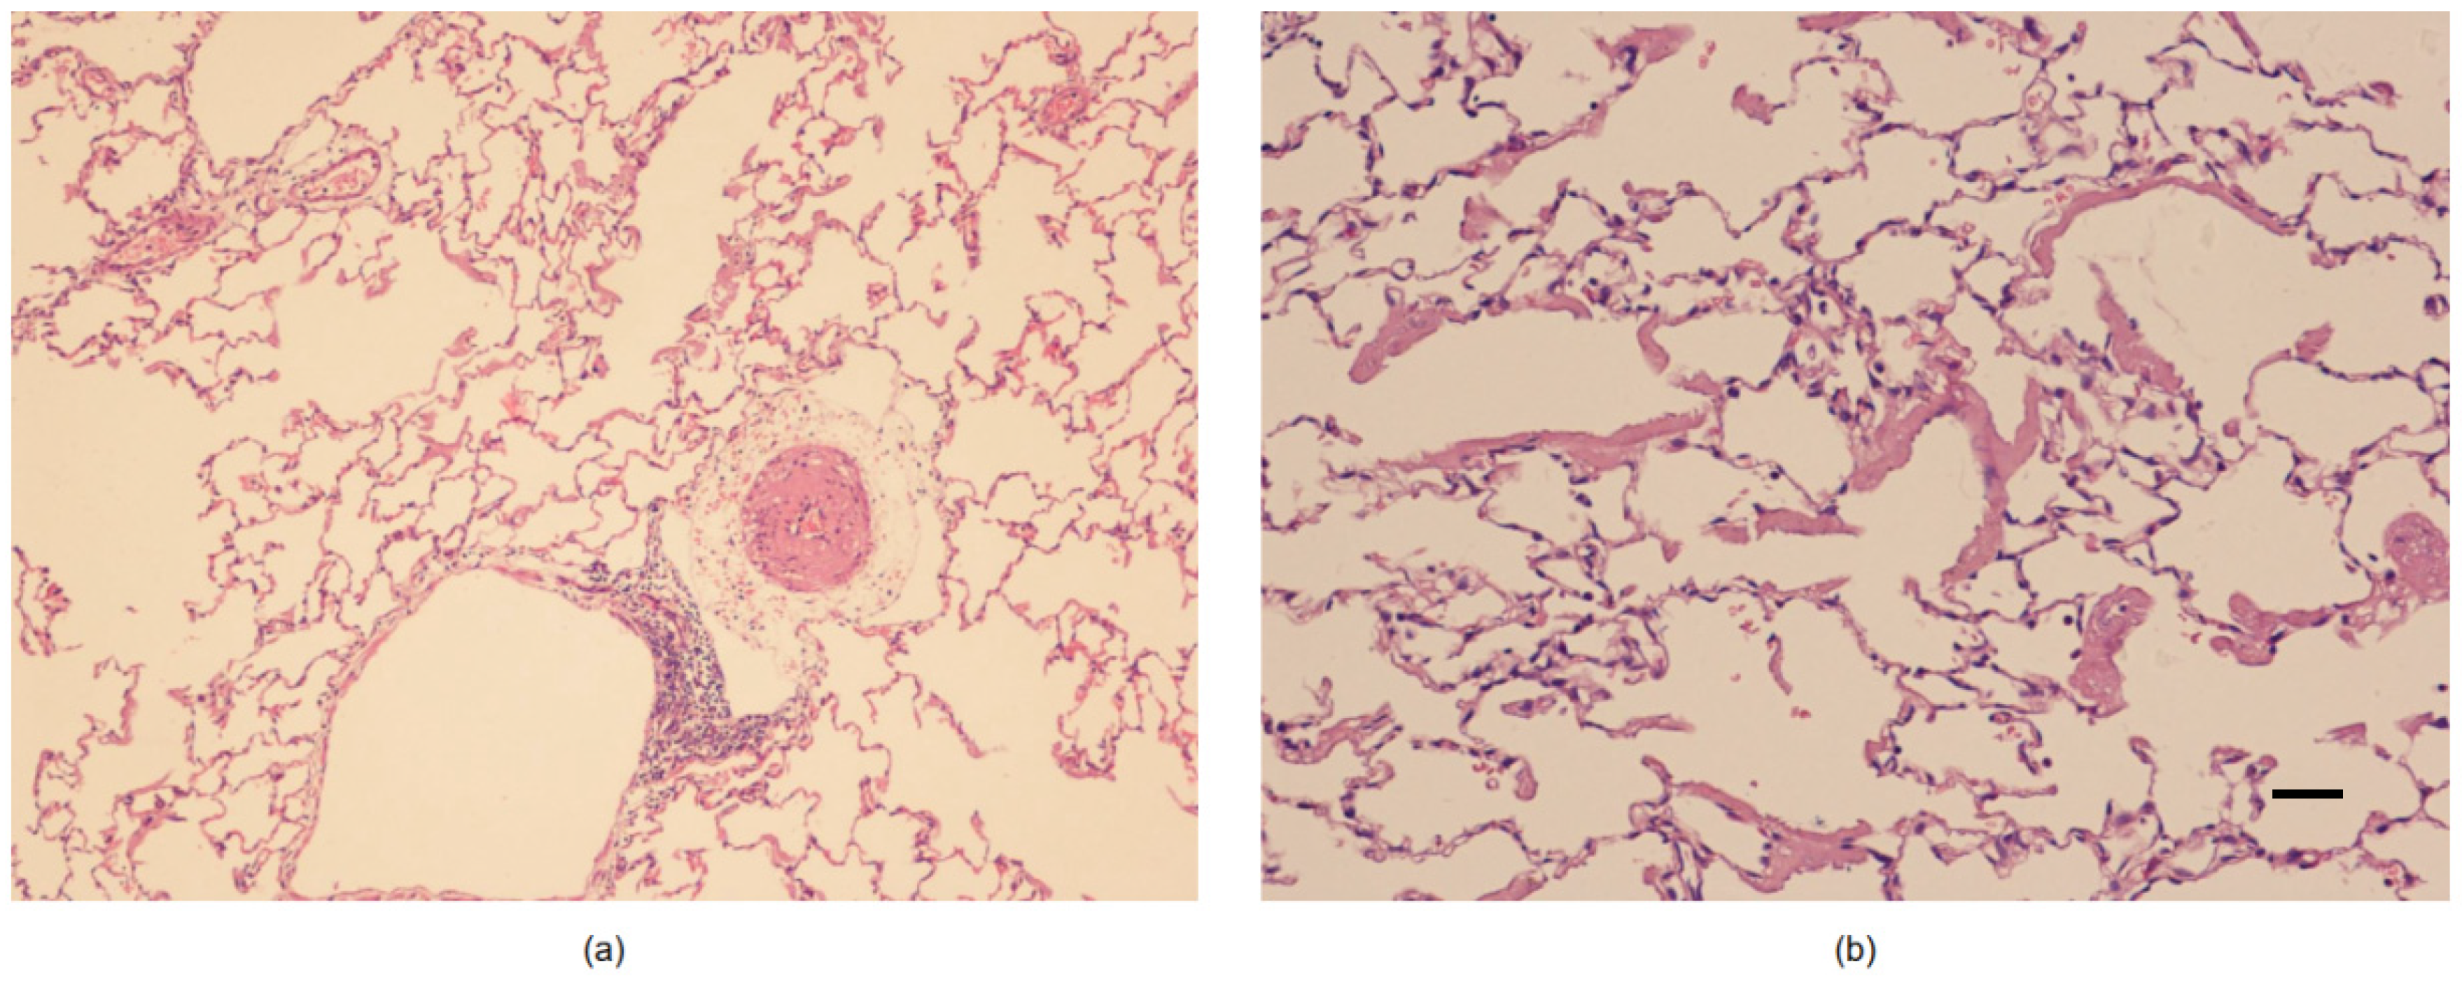

2.6. Histological Study